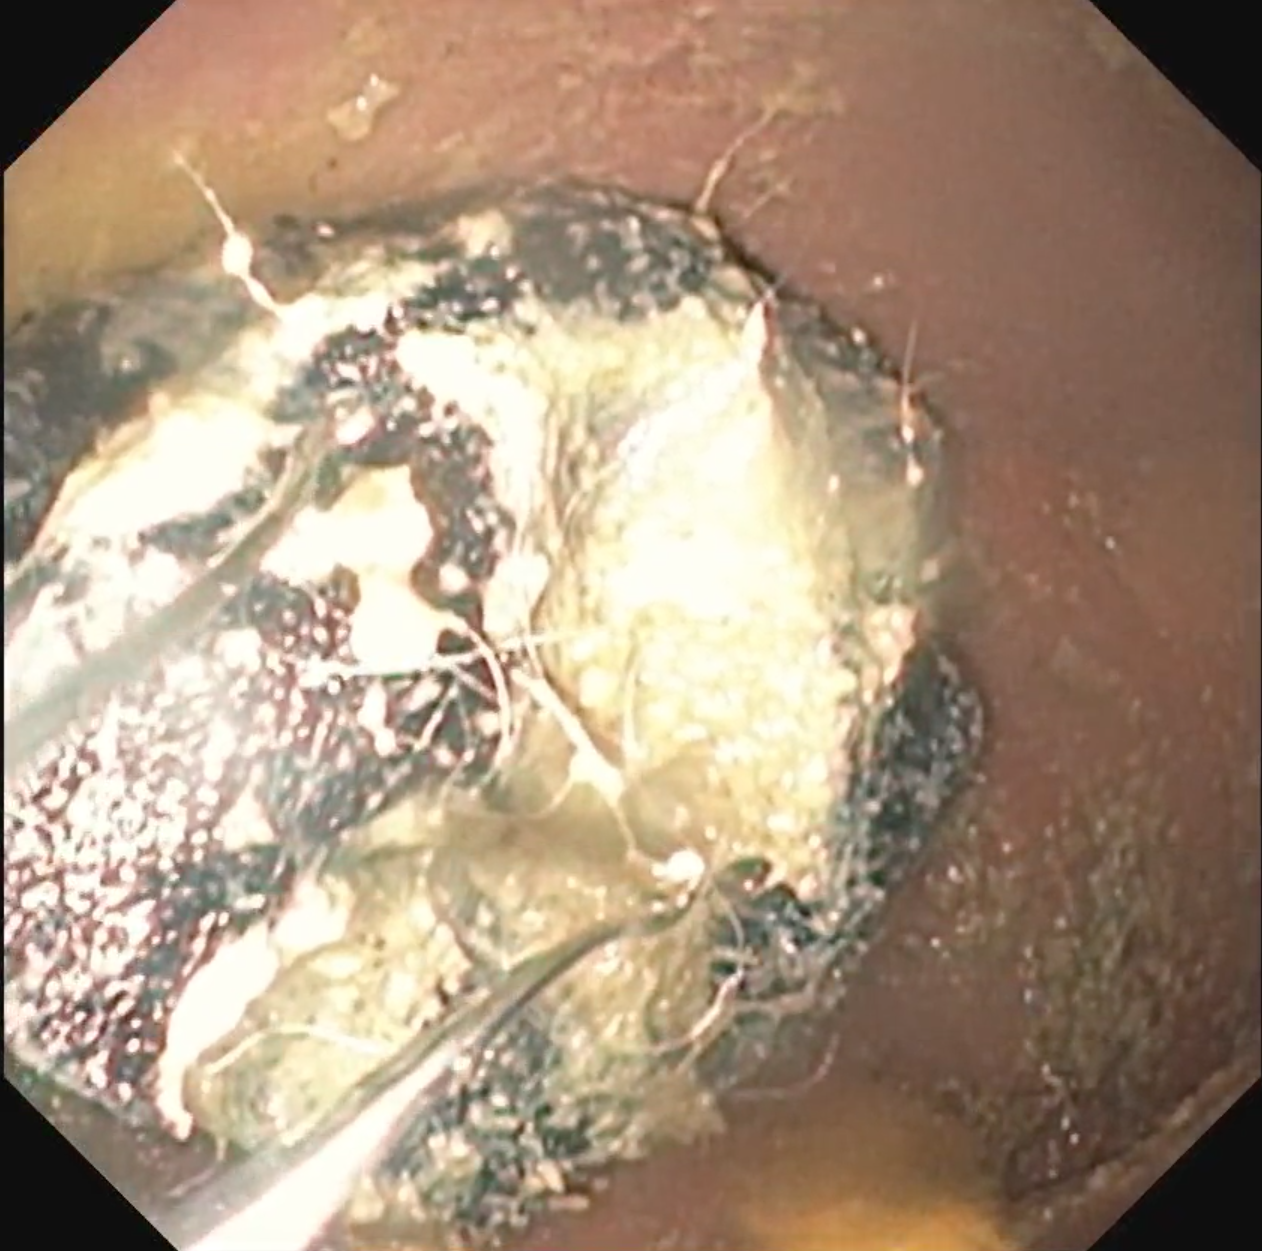

内視鏡を用いて胃内から布製マスクの摘出する様子。画面左下に見える2本の棒状の金属が内視鏡の先端です。 ※マスクは最近非常に増えている異物です